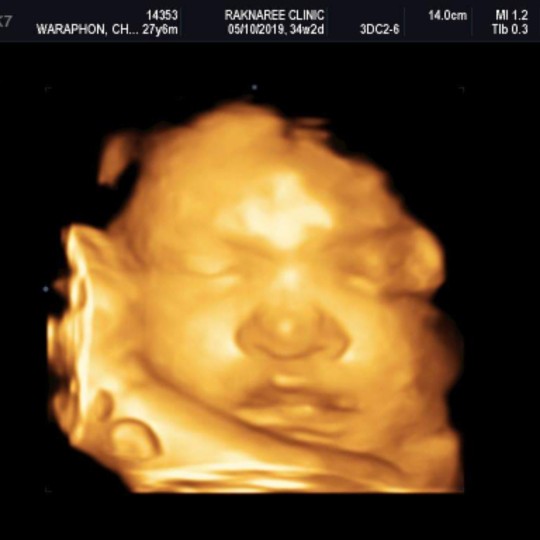

34w2วันค่ะ